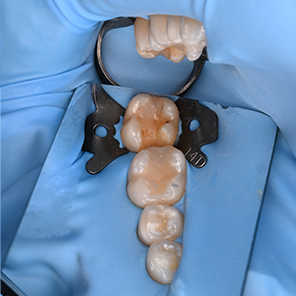

연세일등치과는 만족스러운 수복 결과를 위해, 치료 환경(러버댐)과 신중하게 재료를 선택하는 것, 두 가지를 모두 중요하게 생각합니다.

01. 치료 환경

치과 수복 과정에서 결과의 지속성을 좌우하는 중요한 요소 중 하나는

바로 건조 환경의 유지입니다. 연세일등치과는 레진빌드업 시 러버댐(Rubber Dam)

사용을 원칙으로 삼아, 수복물과 치아의 안정적인 결합을 방해할 수 있는 침(타액)과

미세한 습기, 이물질로부터 치료 부위를 보호합니다.